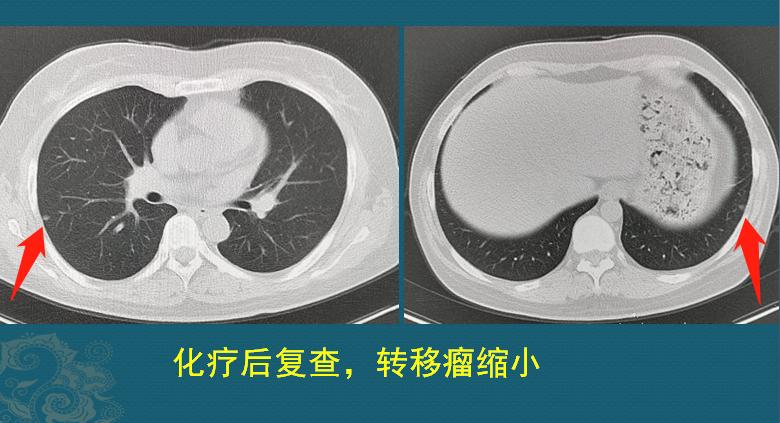

上图是这位女士接受了规范治疗后,第40天复查的肺CT,结节明显缩小,提示治疗有效!